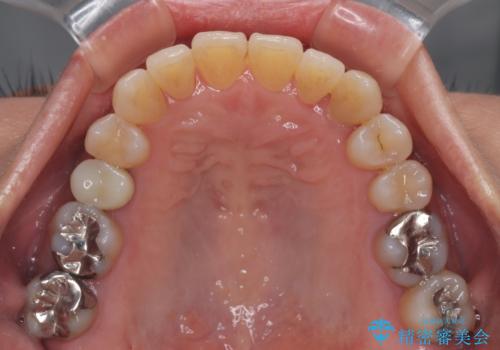

受け口と八重歯を改善 インビザライン矯正治療

受け口傾向のインビザライン矯正は比較的治療を行いやすいため、きれいに仕上げることができました。舌の突出癖が顕著であったため、改善のためのトレーニングをしっかりと行っていただきました。